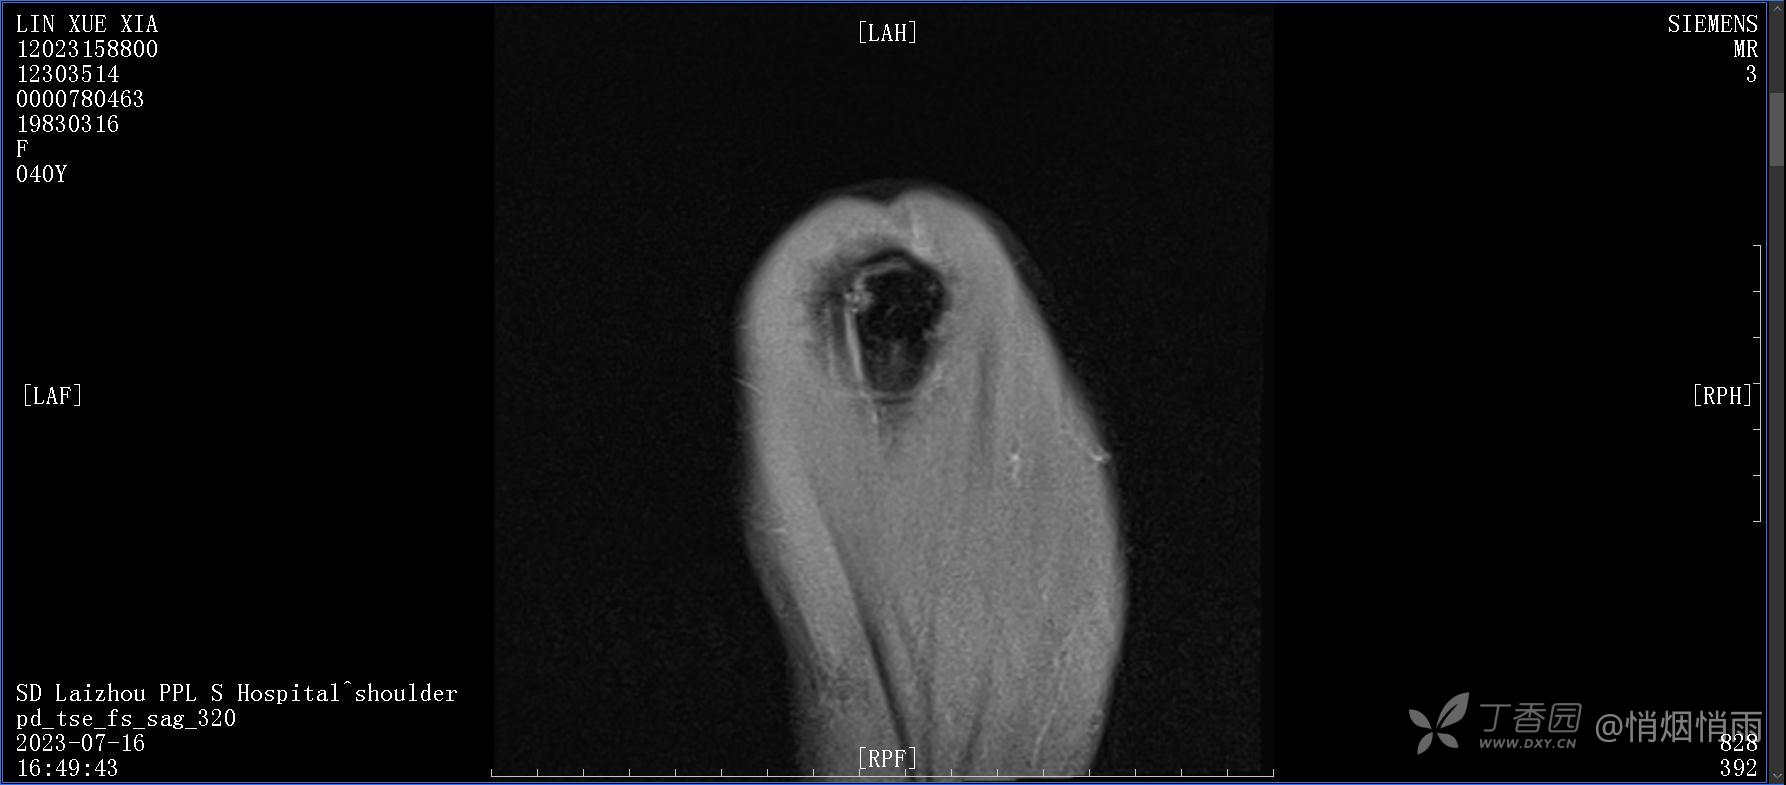

查体:右肩关节局部轻度肿胀,肩胛区压痛明显,痛处不固定,肩关节痛性活动受限,jobe test(+),lift -off test(+),中指、环指感觉较余指减退,余肢端感觉及血运情况可。

目前的诊断,暂时依据辅助检查诊为肩袖损伤,但是患者疼痛的性质和特点,却不是单纯的肩袖损伤所致。考虑过胸廓出口综合征,但是该疾病会出现肩胛区的疼痛吗?(由于考虑到费用的问题,没再进行下一步的检查)带状疱疹会有如此的症状吗?